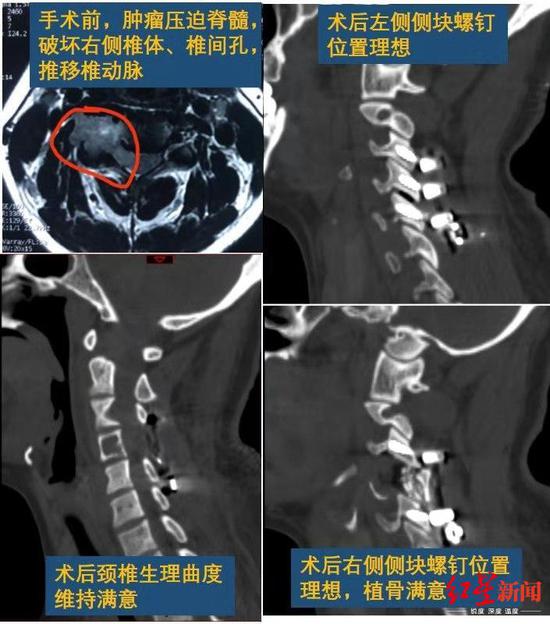

女子手麻头晕一查是颈椎里长个鸡蛋大肿瘤图

图片尺寸550x624